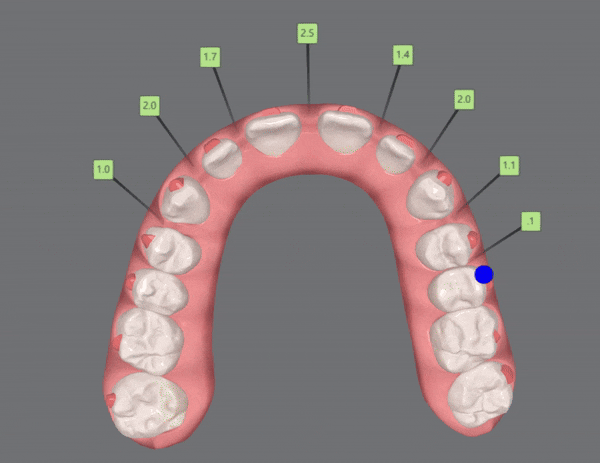

2nd Clincheck

치료기간 24/1~24/6

유펜바른치과의 인비절라인라이트케이스의

두번째 클린체크인 추가 14개의 장치를 통해

인비절라인교정치료가 잘 마무리 되었습니다 :)

치아사이의 공간을 닫을 뿐만 아니라

위, 아랫니의 교합관계도 개선이 되었습니다.